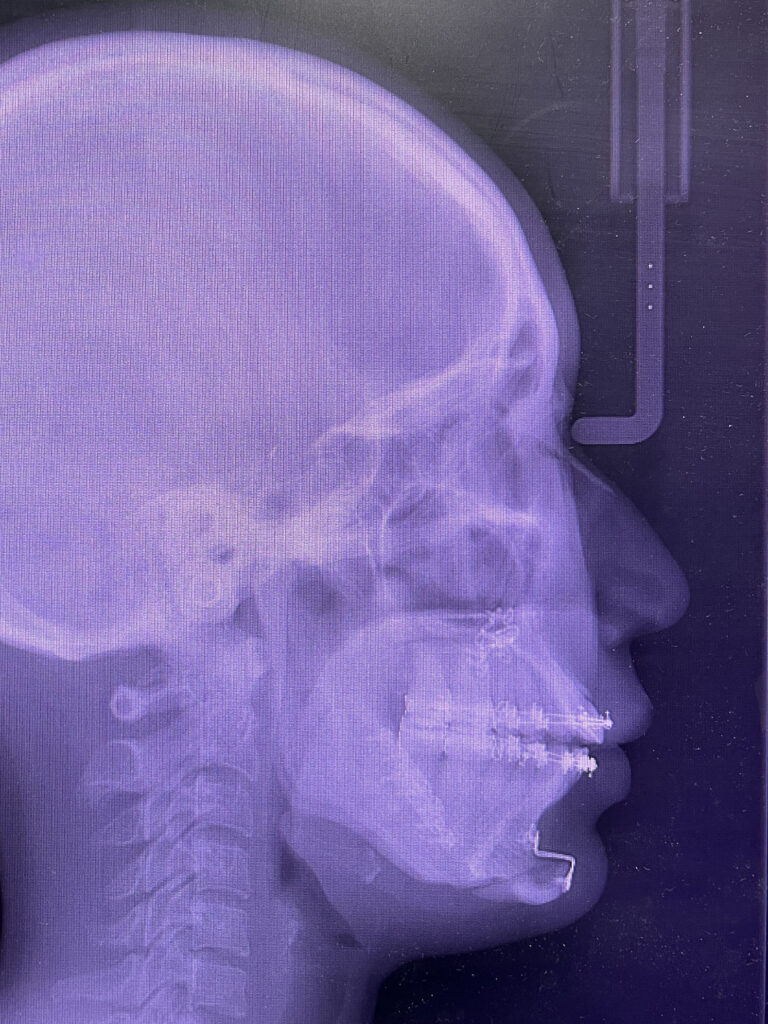

手術は、上あごの位置を整える「ルフォーⅠ型骨切り術」、下あごの位置を調整する「下顎枝矢状分割術」、そしてあご先を前に出す「オトガイ形成術(前進術)」を同時に行いました。

上あごは全体を後方へ3mm移動し、さらにわずかに回転を加えることで、開咬がしっかり閉じるよう調整しています。

あご先(オトガイ)は10mm前方へ移動させ、横顔のバランスを整えました。

口元の突出感もやわらぎ、さらにあご先(オトガイ)を前に出すことで、横顔のバランスも大きく改善しています。